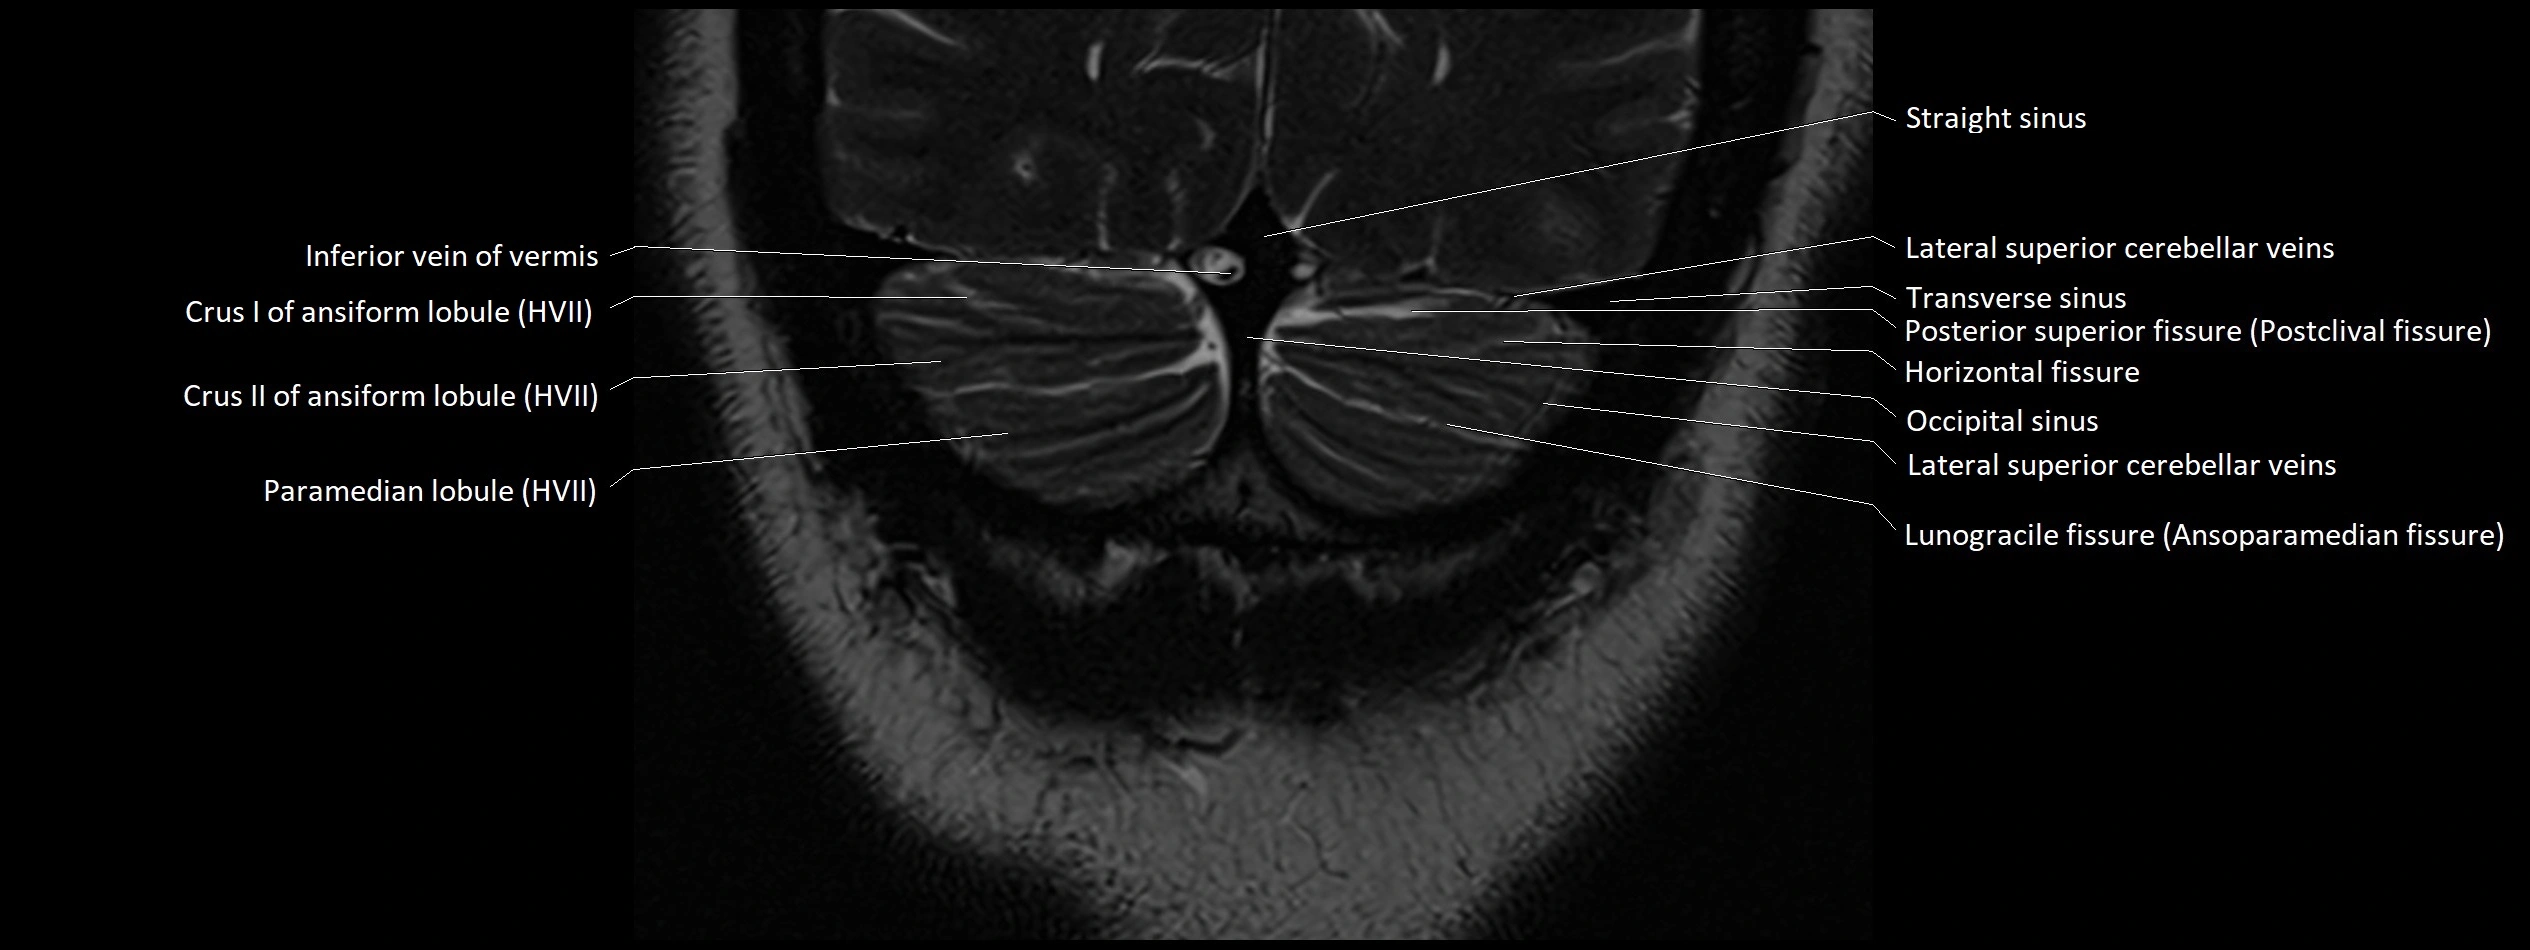

- Crus I of ansiform lobule of cerebellum

- Crus II of ansiform lobule of cerebellum

- Horizontal fissure (cerebellum)

- Inferior vein of vermis

- Lunogracle fissure

- Lunogranicile fissure of cerebellum

- Occipital sinus

- Paramedian lobule

- Paramedian lobule (HVII) of cerebellum

- Posterior superior fissure

- Straight sinus

- Superior cerebellar vein

- Superior hemispheric cerebellar veins

- Superior hemispheric veins of the cerebellum

- Transverse sinus